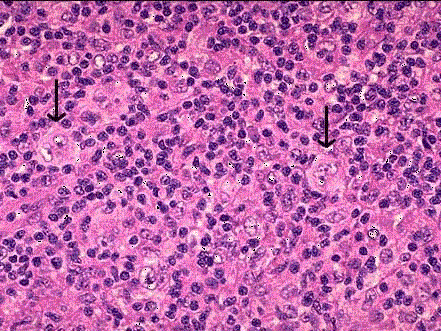

图霍奇金病镜下观,箭头所指为肿瘤细胞。 该细胞多见于哪一类霍奇金病 ( )A.混合细胞型和结节硬化型B.淋巴细胞为主型C.混合细胞型...

问题 图霍奇金病镜下观,箭头所指为肿瘤细胞。 该细胞多见于哪一类霍奇金病 ( )

选项 A.混合细胞型和结节硬化型 B.淋巴细胞为主型 C.混合细胞型和淋巴细胞减少型 D.淋巴细胞减少型 E.结节硬化型

答案 C